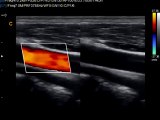

Carotid Triplex Chison Q9

Chison Q9 Ultrasound Quardplex combines B, color, and PW with automatic trace and measurement to make accurate diagnosis. Updated in real time. www.keebomed.com